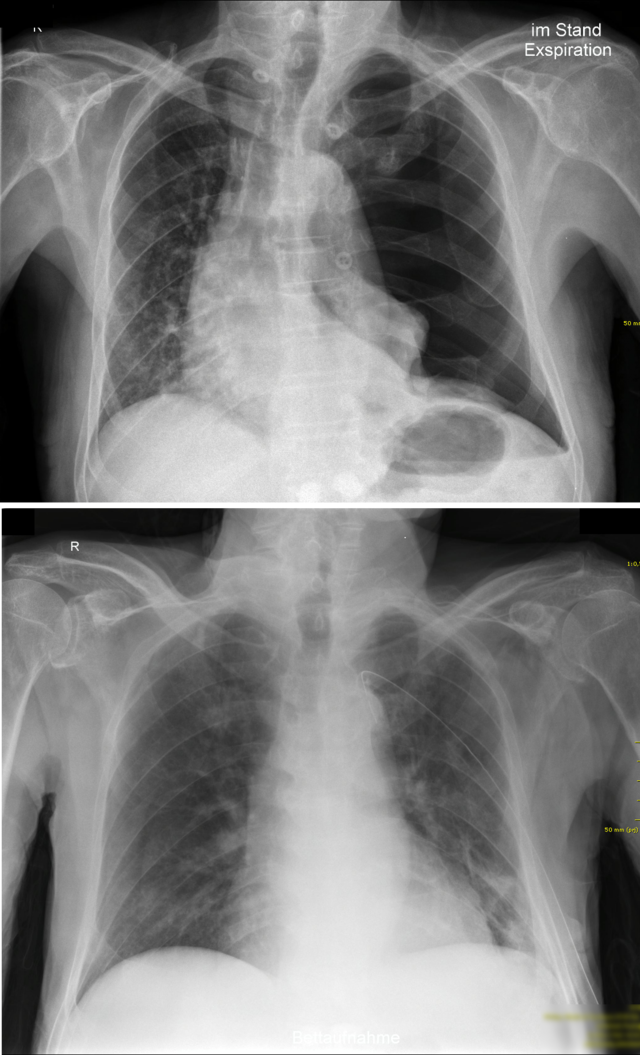

Ein linksseitiger Spannungspneumothorax vor (oben) und nach (unten) Anlage einer Thoraxdrainage. Gut zu sehen ist die Verlagerung des Mediastinums hin zur gesunden Seite. © wikipedia.org/Cupr78up, CC BY-SA 3.0

Am besten lässt sich ein Pneumothorax im Röntgenthorax (in Expiration und Inspiration) oder im CT darstellen.